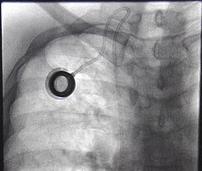

The FDA has issued a Class 1 recall of 2 million huber needles because of a coring problem resulting from defect in the manufacturing and design process. The huber needles are manufactured by Nipro Medical Corporation and distributed by Exelint International Corporation.

The FDA advises healthcare professionals to take the following precautions when using any type of Huber needle (ie, not just those manufactured by Nipro) in conjunction with normally operating ports:

* Avoid flushing the syringe when confirming patency of the needle on accessing the port, as it may introduce a silicone core into a patient’s body.

* Consider aspirating blood after accessing the port and then discard the syringe with its contents. This step may recapture the silicone sliver. If the needle becomes clogged, use a new one.

* Watch for indications of damage to the port’s septum. These include medication leakage, resulting in inadequate dosing as well as tissue damage, and localized erythema.